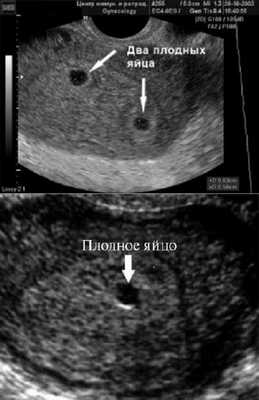

Самый ранний срок, на котором можно разглядеть с помощью трансвагинального УЗИ плодное яйцо в полости матки - это 30-й день гестации, или 4-5 акушерских недель беременности. Уровень ХГЧ крови при этом должен быть не менее 1000 мЕд/мл. В это время ещё не видно ни эмбриона, ни желточного мешка. При визуализации двух плодных яиц можно утверждать, что это дихориальная многоплодная беременность. При визуализации одного плодного яйца можно утверждать, что это монохориальная беременность. Но на этом сроке мы ещё не можем сказать сколько эмбрионов находится в каждом плодном яйце. Кроме того, во время однократного УЗИ мы ещё не можем сказать, прогрессирует ли данная беременность, так как у эмбриона ещё нет сердцебиения. Средний внутренний диаметр (СВД) плодного яйца на этом сроке 2-10 мм.